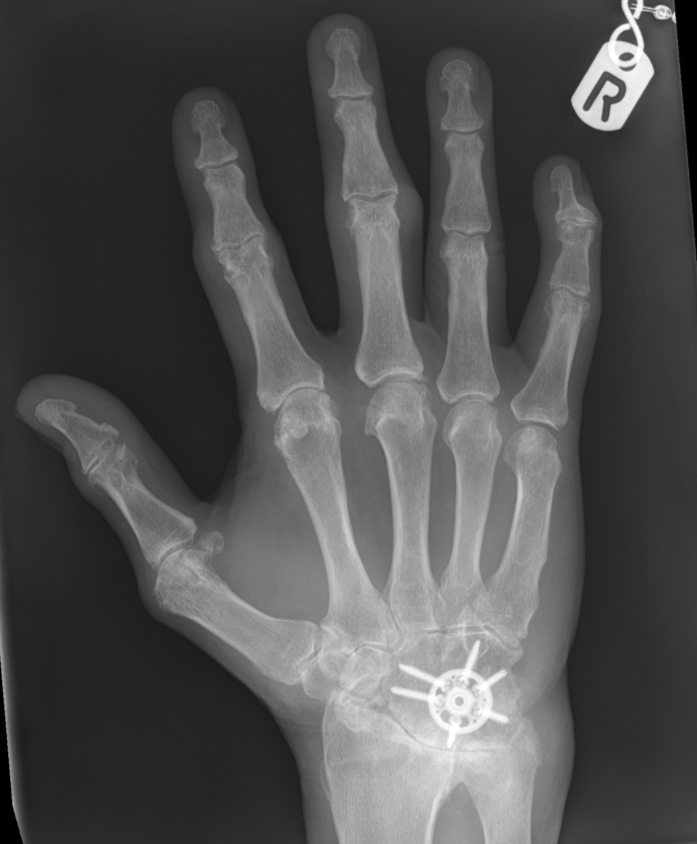

3. 4-Corner carpal fusion of wrist